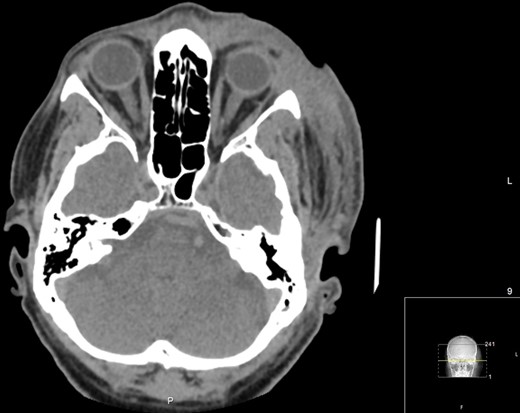

A 60-year-old male with a past medical history of hypertension presented to the emergency department of a District General Hospital with a 7-day history of a worsening left eye swelling, pain and erythema. There was no history of previous trauma, sinus disease or recent surgery. On arrival, clinical examination revealed that the patient was in circulatory shock with signs of sepsis. Immediate treatment for a suspected septic shock due to left periorbital cellulitis was started with broad-spectrum intravenous (IV) antibiotics (Vancomycin, Gentamycin, Meropenem and Clindamycin), aggressive fluid resuscitation and oxygen supplementation. A computed tomography (CT) carotid angiogram revealed a diffuse left orbital cellulitis with no intraorbital collection (Fig. 1A). There was no evidence of intracerebral vascular thrombosis (Fig. 1B). Blood tests showed an inflammatory picture (Table 1).

Axial CT angiogram carotids images showing (A) diffuse left periorbital region involvement with no retro-orbital or extra-orbital collections. (B) No evidence of vessel thrombosis.